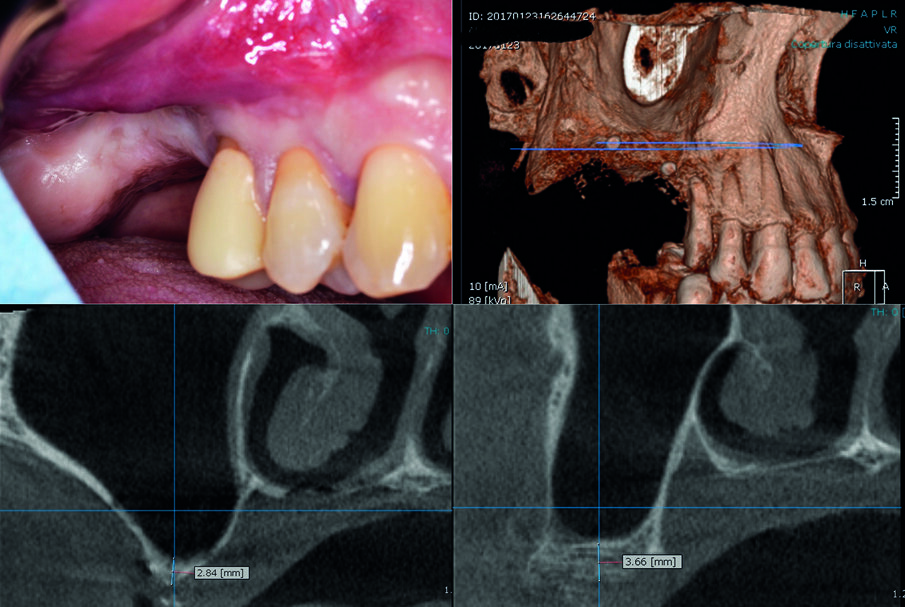

Il paziente (A/M, 60 anni) presentava una marcata atrofia verticale a carico dell’arcata superiore destra in posizione 1.6 e 1.7 (Fig. 1). Un’attenta valutazione del caso portava ad escludere l’opportunità di eseguire un intervento di rigenerazione ossea guidata (GBR) in senso verticale; il paziente infatti presentava un fornice quasi totalmente assente, i piani anatomici completamente sovvertiti per pregressi interventi chirurgici nel primo quadrante, una limitata apertura orale e, in aggiunta, una scarsa compliance. Al paziente è stato quindi proposto un piano di riabilitazione impianto-protesica basato sull’inserimento di due impianti in associazione ad una tecnica idropneumatica di rialzo del seno mascellare per via crestale su siti multipli, eseguito attraverso l’innesto della pasta ossea precedentemente descritta.

L’area di intervento è stata anestetizzata utilizzando articaina cloridrato 40 mg con adrenalina 1:100000. Si è proceduto quindi a sollevare un lembo trapezoidale a tutto spessore mediante un’incisione crestale anticipata palatalmente. Dopo avere posizionato una dima radiologica, appositamente fabbricata, si è proceduto a marcare i siti implantari sulla corticale ossea in corrispondenza dei reperi metallici, e a preparare i tunnel implantari per mezzo del sistema “Crestal Approach Sinus Kit” (BetaPharm, Via Brigata Berto 10 - 16030 Cogorno - Italia). Da notare che l’altezza ossea residua (Residual Bone Height o RBH) inferiormente al seno mascellare variava tra i 3,66 mm e i 2,84 mm.

Fig. 1 - Aspetto clinico e radiografico dell’arcata superiore destra del paziente alla prima visita. La zona corrispondente agli elementi 1.6 e 1.7 presente una grave atrofia ossea verticale.